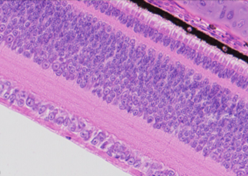

您的位置:首页 >> 产品介绍 >> 鸡眼球HE扫描切片

鸡眼球HE扫描切片

鸡眼球HE图片描述:色素上皮细胞层、感光细胞层、双极细胞层、节细胞层,各层细胞结构排列整齐,形态良好,未见断裂,细胞间无裂隙,细胞核清晰可见,节细胞层排列整齐紧密,节细胞条带、感光细胞层密度及宽度正常。